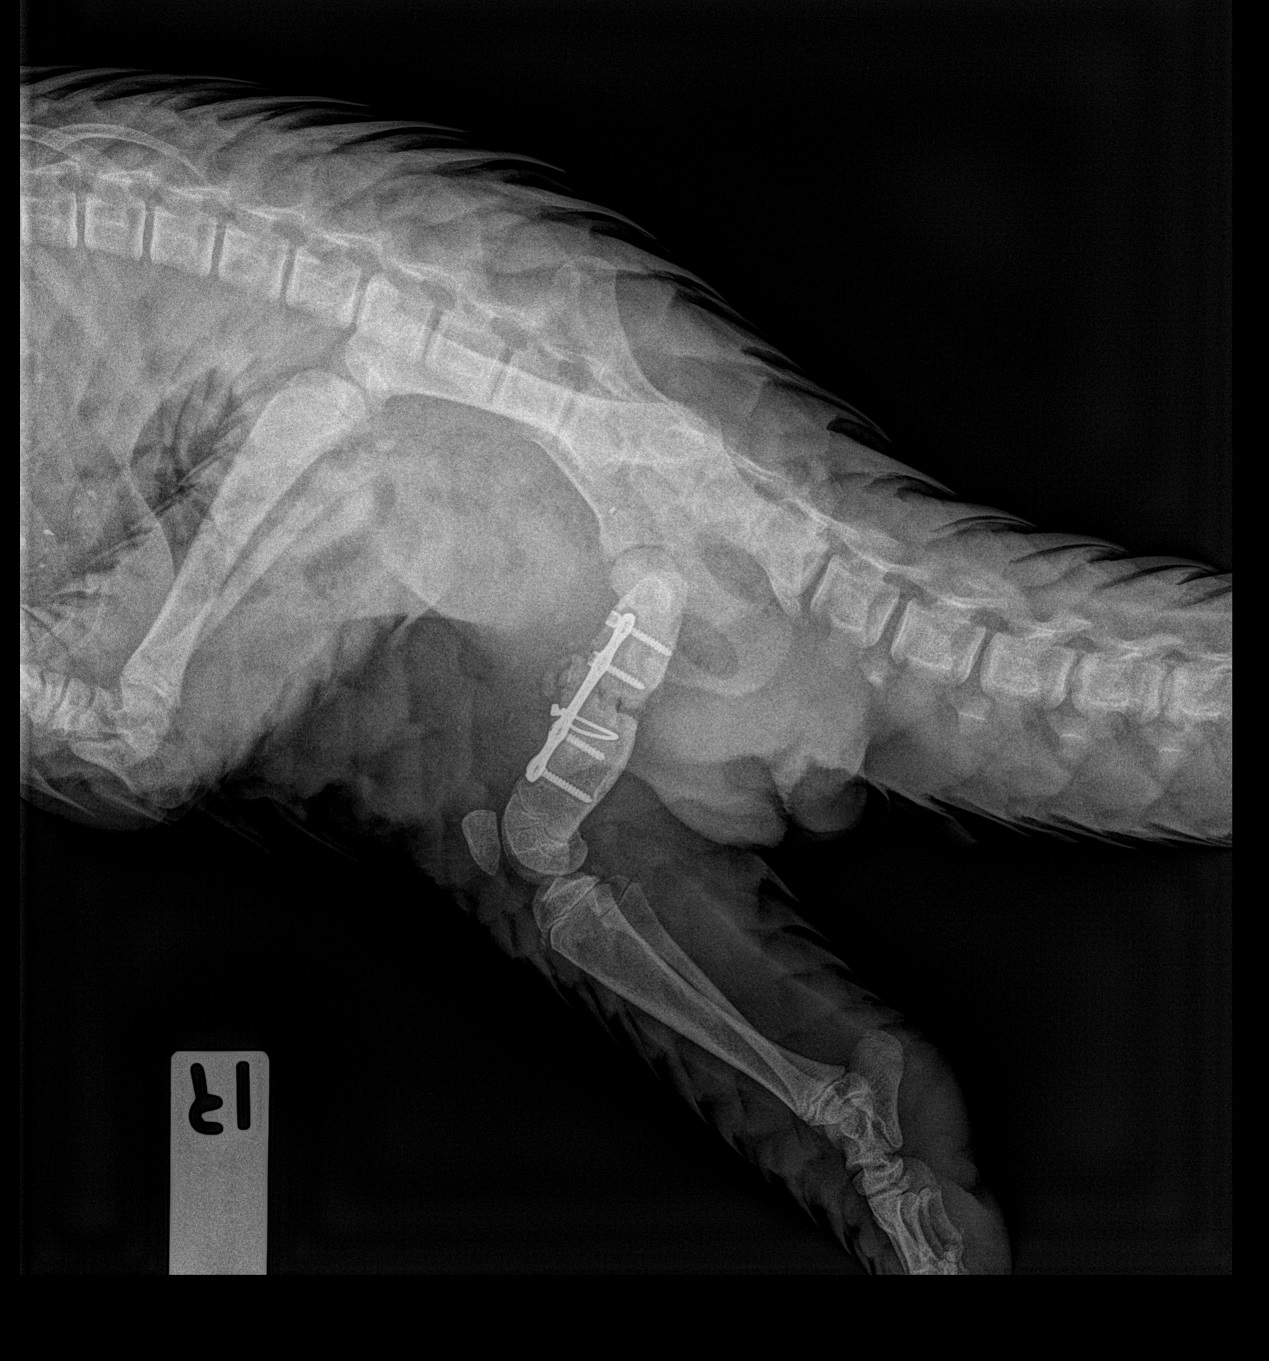

Close-up of Berani’s X-ray taken on 28 Jan 2019 showing that the implants are in place and that bone healing has been recorded.